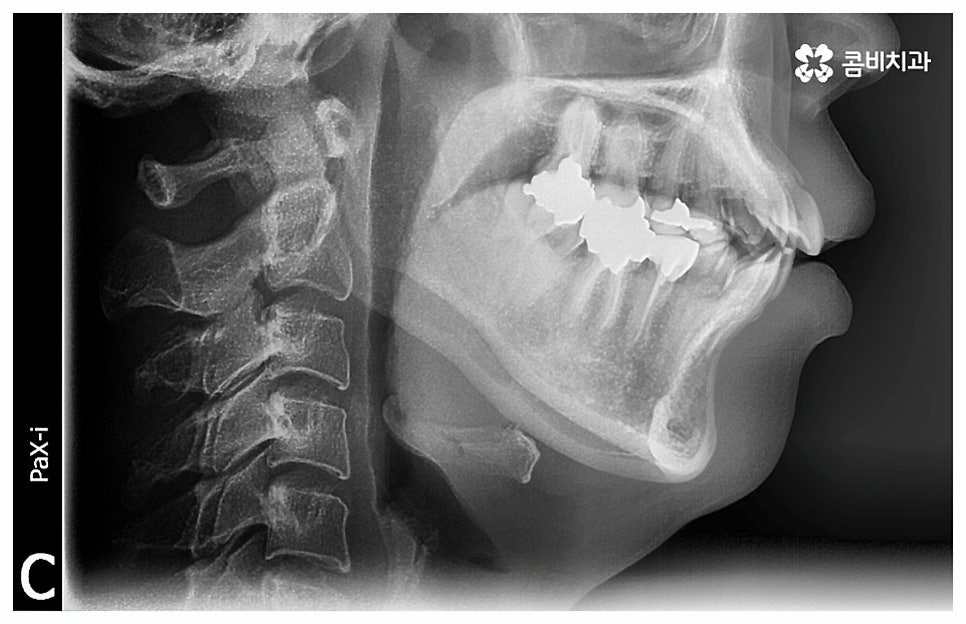

즉 중장년기에는 이미 골격이 완성된 상태이기 때문에 치아 이동 속도가 느려서 청소년기에 교정을 시작하는 것보다 전체 치료 기간이 조금 더 오래 걸릴 수 있으나 치아 교정이 아예 불가능한 것은 아니기 때문에 하고 싶다는 생각이 든다면 먼저 치과에 내원하셔서 자신의 상황에 대해 꼼꼼하게 검진부터 받아 보시길 권유드리고 있어요. 이때 3D CT 와 같은 정밀 검진 장비를 갖춘 치과라면 더욱 편안한 마음으로 검진 및 상담에 임하실 수 있을 거예요.

위 사진은 환자분의 동의를 받아 이해를 돕기 위한

사진이며, 실제 치료 결과는 다를 수 있습니다.